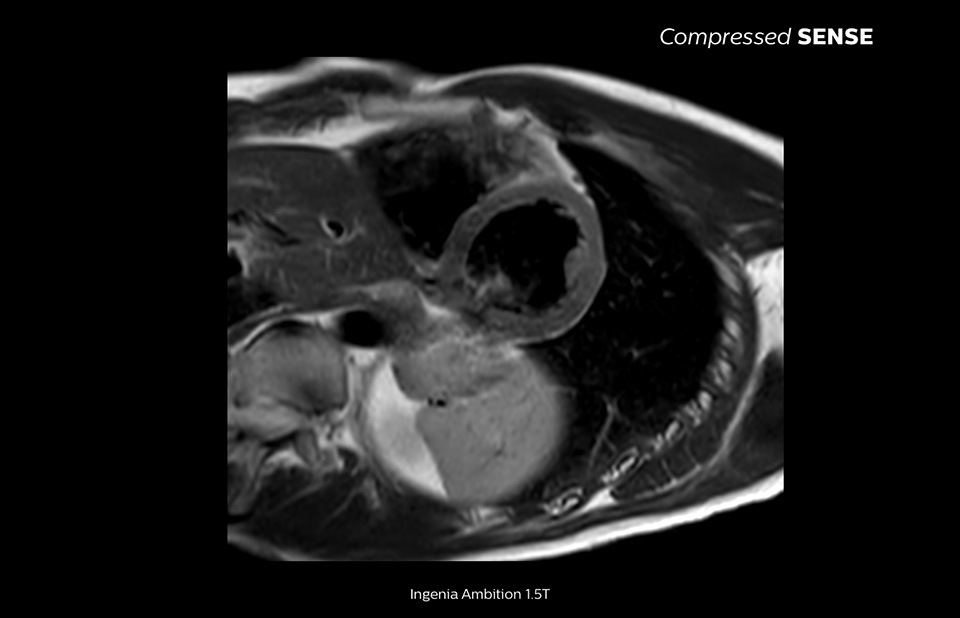

Philips Compressed SENSEを使用すると、MR検査時間を短縮できます。さらに、Compressed SENSEでは息止め時間を短縮できるため、MR検査の質を向上させることができます。

息止め時間、4.8秒

患者にとって息止め時間が短い方が負担が少なく、息止めの失敗が大幅に減少します。

15~16秒におよぶ息止め時間は、心疾患患者にとって苦痛となることがあります。Compressed SENSEには、息止め時間10秒未満のプロトコルが実際に搭載されています。息止め時間が短いほうがはるかに楽なので、検査の満足度が大幅に向上します」

Trevor Andrews博士、MR技師、バーモント大学メディカルセンター、米国

消化器腫瘍科では長時間の臥位が困難な患者もいるため、Compressed SENSEのスキャン時間は大きな意義を持つと思います。なぜなら、こうした患者は痛みがあったり、呼吸サイクルが低下していたりするためです。たとえば、ダイナミックmDIXONシーケンスでの息止め時間は12~13秒ですが、これを9秒まで短縮できれば、患者は非常に楽になるでしょう。そして、それが画像品質の向上にもつながります」

Christoph Juli医師、Spitalklinikum Spital Uster、スイス